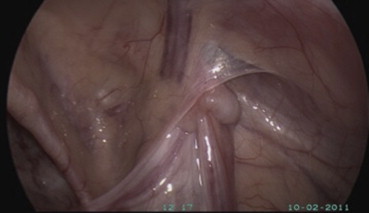

Prior to being referred to the UKM Hospital Pediatric Surgery Outpatient Department, 23 patients with impalpable testes presented for laparoscopy after having undergone ultrasound. No testes were identified on ultrasound examinations. Five patients had palpable testes in the superficial inguinal pouch under anesthesia, and proceeded to conventional open exploration during which the testes were brought into the scrotum without tension. Eighteen (18/23) patients had impalpable testes in an evaluation under anesthesia (EUA) and proceeded to laparoscopy. Twelve patients had intra-abdominal testes and underwent laparoscopic-assisted orchidopexy (Fig. 2). Three patients underwent the two-stage Fowler–Stephens procedure. Two patients with vanishing testes with the vas deferens and atrophic vessels entering a closed internal ring proceeded to open exploration and orchidectomy for atrophic testes (Fig. 3). In addition, a teenager with atrophic testes underwent laparoscopic orchidectomy.

Intra-abdominal testis. The testis is located at the outer ring of the inguinal ...

Figure 2.

Intra-abdominal testis. The testis is located at the outer ring of the inguinal canal.